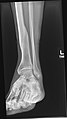

The left leg, with the medial malleolus labeled at bottom right.